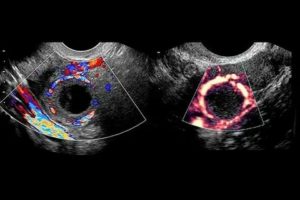

Как проходит диагностика

Врач может определить причину запоздания кровотечения уже на начальном этапе диагностики, во время обычного осмотра. Однако чтобы убедиться в точности поставленного предварительно диагноза дополнительно назначается УЗИ. С помощью ультразвукового исследования выявляется размер опухоли, ее локализация, делается предположение о типе новообразования и способе лечения.